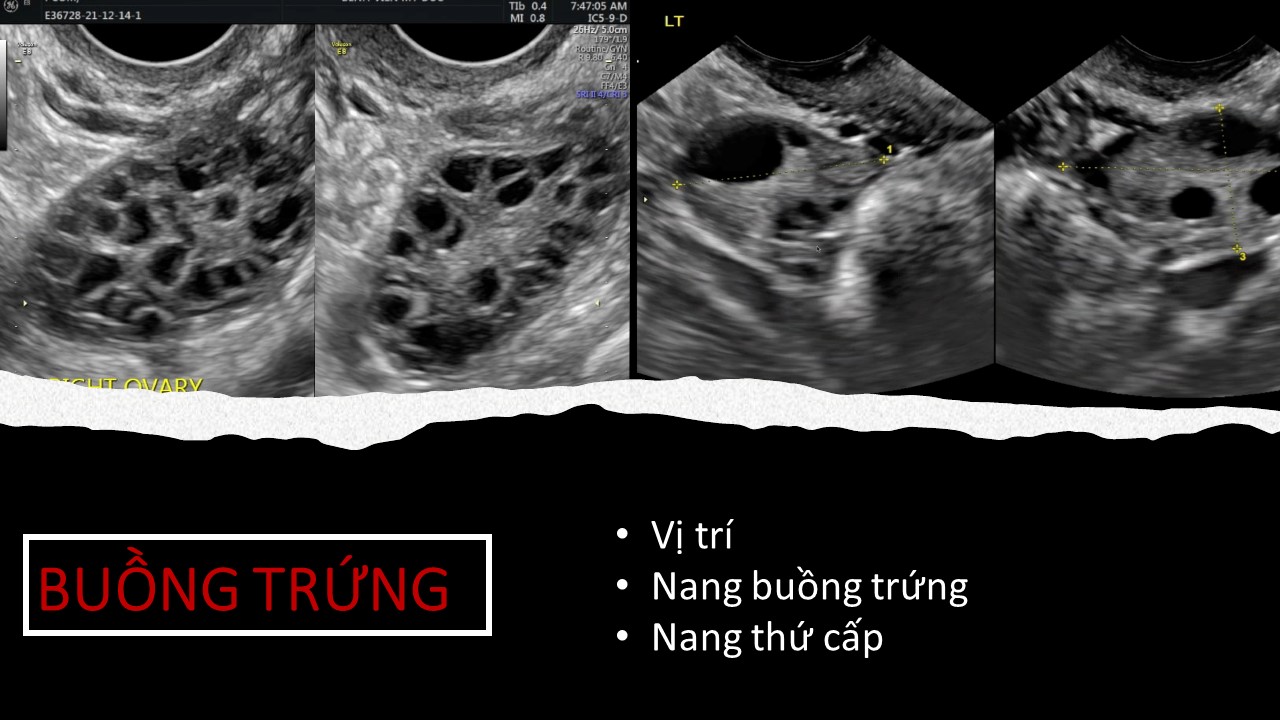

Vai trò của siêu âm trong chẩn đoán và điều trị hiếm muộn